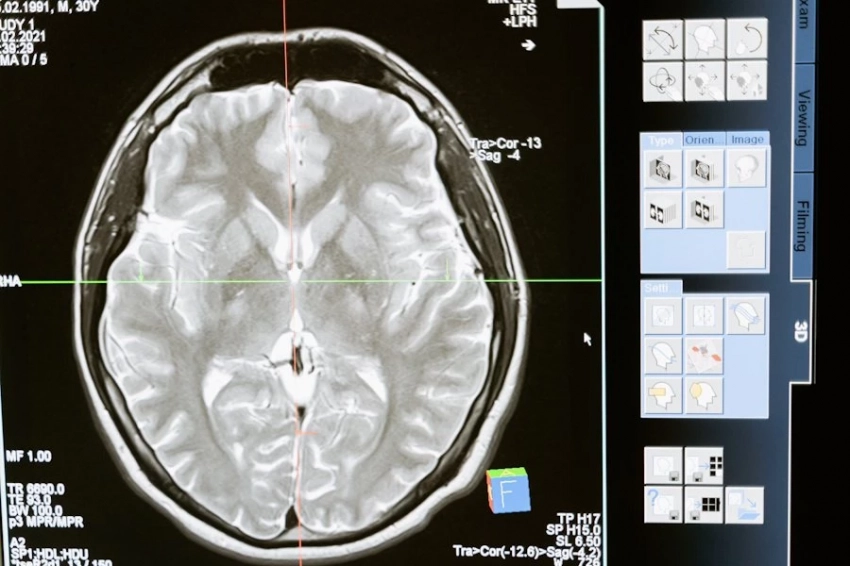

Врачи в Израиле начинают применять новые технологии, препараты и терапевтические схемы на 4–6 лет раньше, чем это становится общепринятым в мировой практике. Диагностика здесь быстрее, точнее, а подход к терапии — мягче, безопаснее и эффективнее.